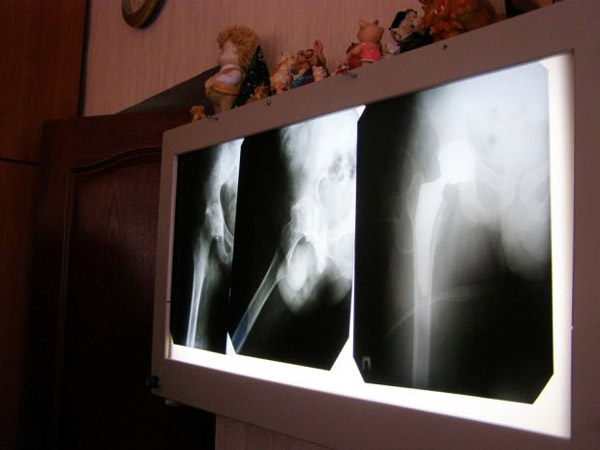

Лечащий врач Андрея Иван Забелин на рентген-снимках наглядно продемонстрировал, как хирургам удалось обеспечить существенное улучшение качества жизни молодого человека.

- Операция была сложной. Для установки имплантата и обеспечения в последующем всей полноты движения сустава нам довелось произвести ревизию и костную пластику, - рассказал Иван Николаевич. - В составе операционной бригады работали 4 хирурга, анестезиолог, операционные сестры. Сама операция была довольно длительной. Но сегодня, спустя лишь неделю после нее, мы уже выписываем пациента домой. Первое время он будет еще пользоваться костылями при передвижении. Но уже через пару месяцев сможет ходить самостоятельно.